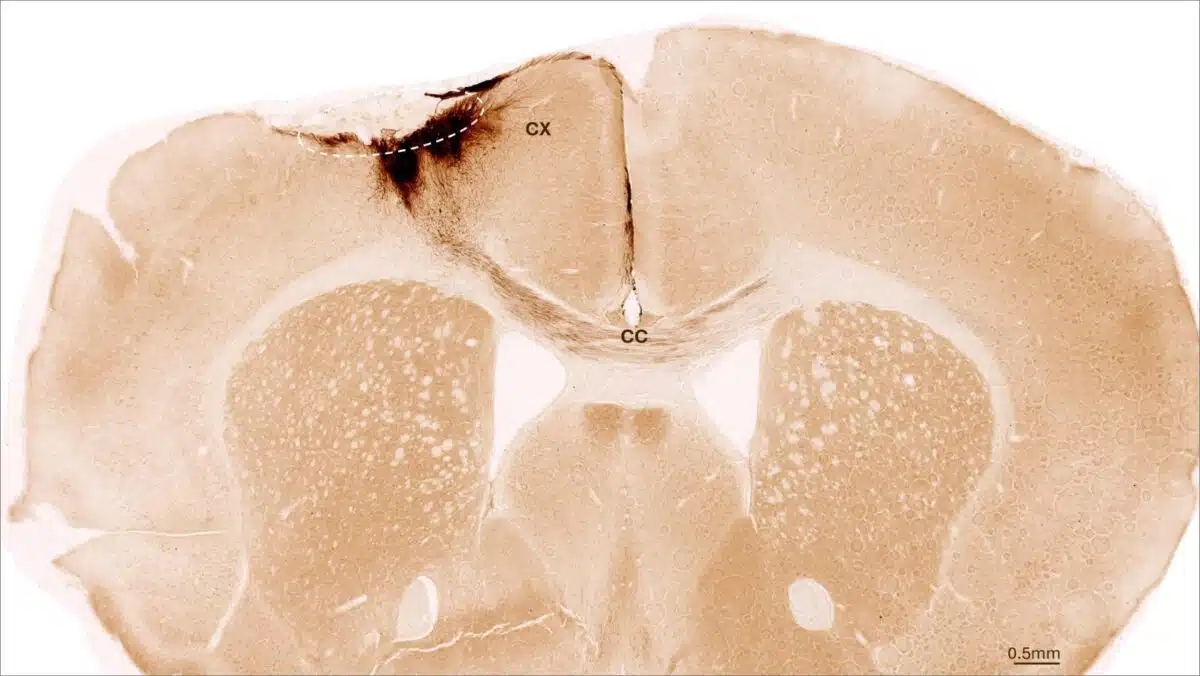

뇌졸중을 겪은 뒤 인간신경줄기세포 이식을 받은 실험실 쥐 뇌의 관상면 단면. 점선 원은 뇌졸중 부위이며, 이식된 인간신경줄기세포의 신경돌기(짙은 갈색)가 피질(CX)까지 국소적으로 뻗어 있을 뿐만 아니라, 뇌량(CC)을 통해 반대쪽 뇌반구까지 뻗어 있다. 취리히대학교 제공